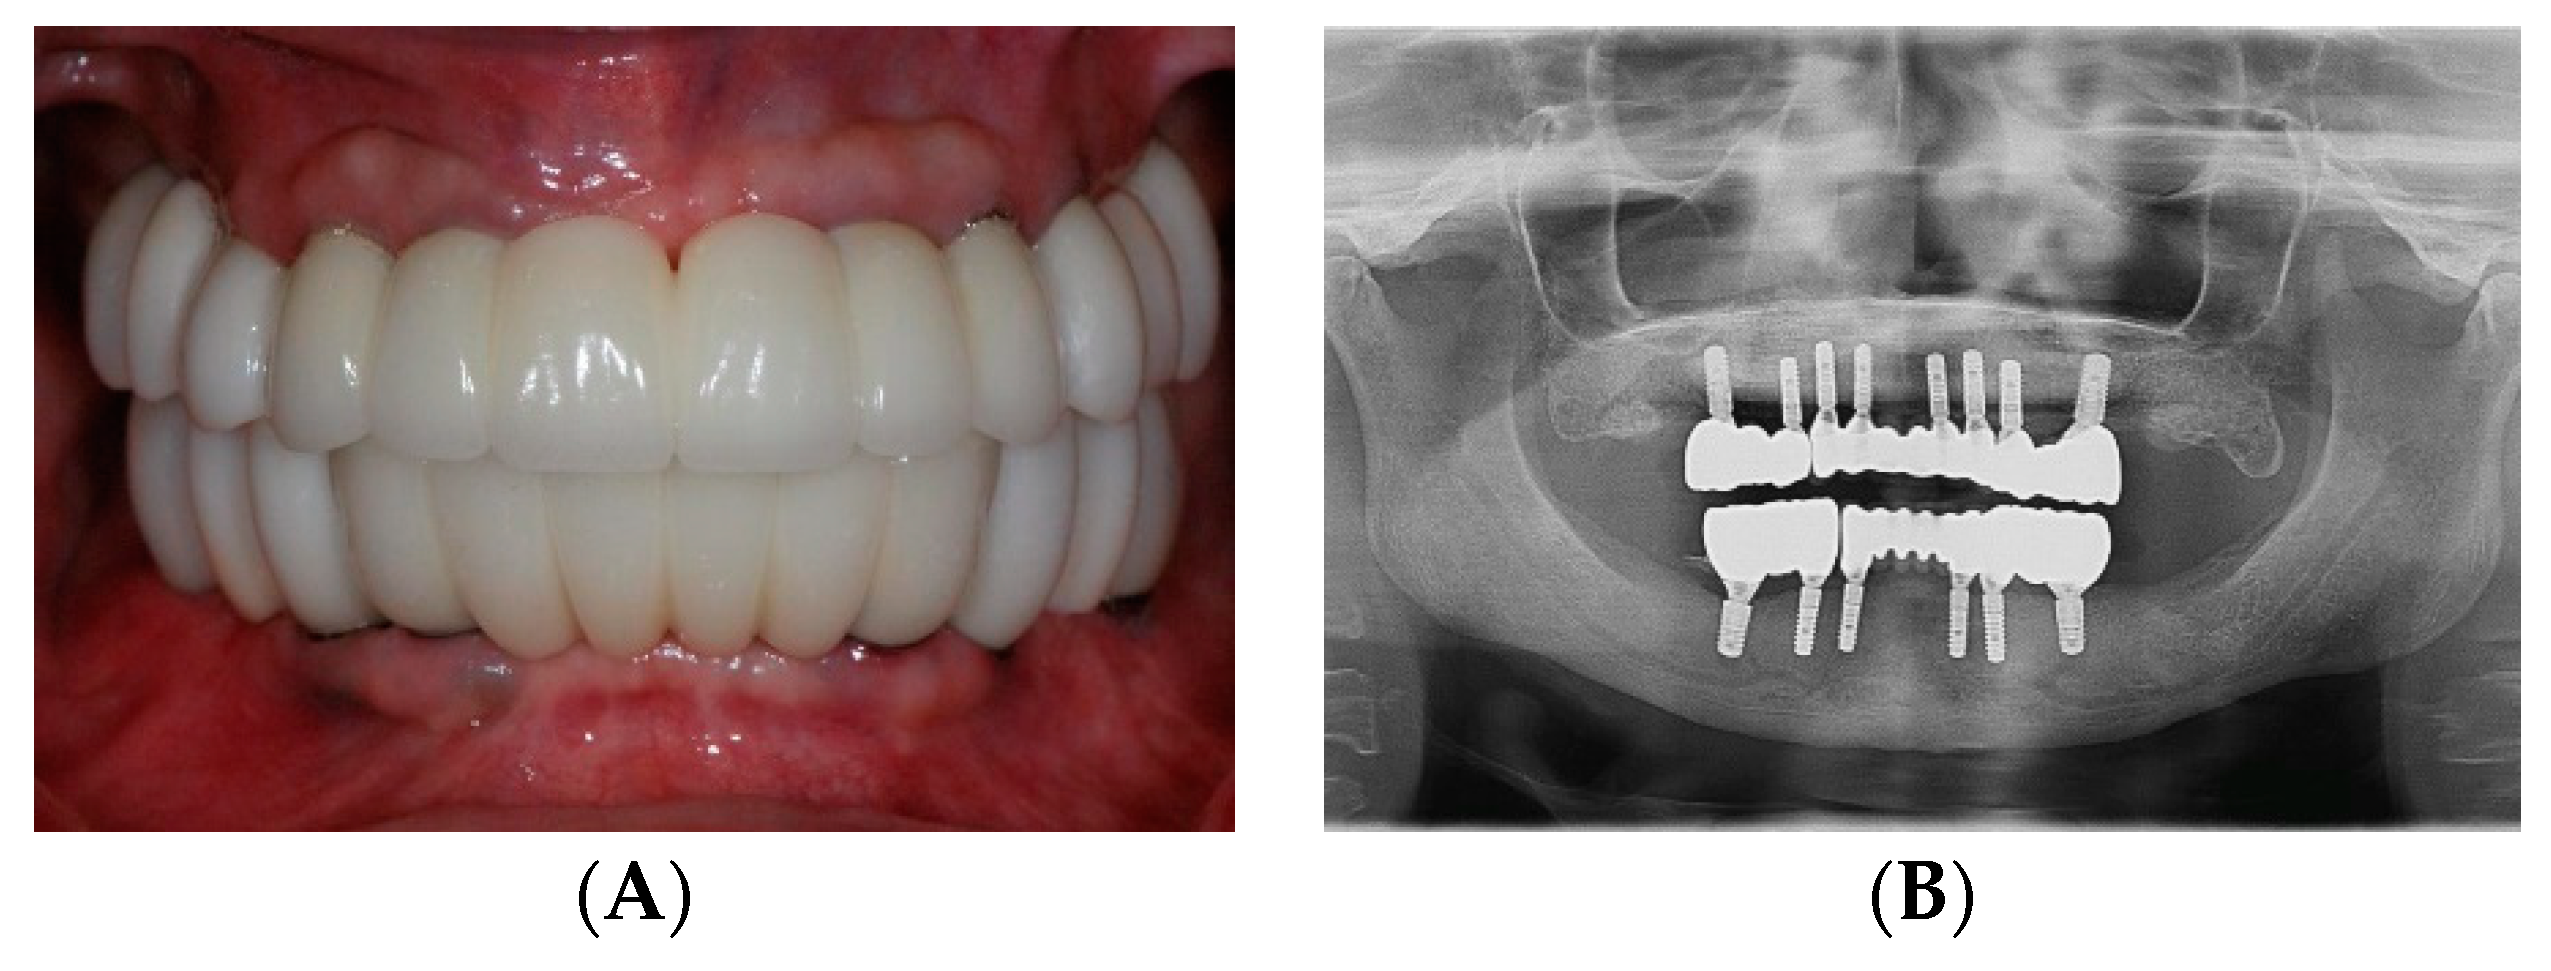

2.2. Foundational Phase: Elimination of Active Disease, Extraction and Fixed Provisional Prosthesis

2.3. Surgical Phase: Virtual Planning of Implant Placement and Computer Guided Surgery

2.4. Restorative Phase: Second Strategic Extraction and Conversion of Provisional Prostheses with Integrated Digital Workflow